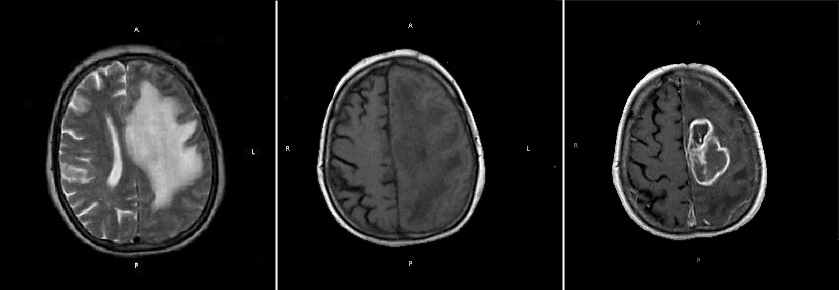

У

123 (79,8 %) пациентов метастазы выглядели как узлы (рис.1), у 15 (9,7 %) – как кисты с усиленным на Т2 ВИ-сигналом.

Рис. 1. МРТ одиночного метастаза рака почки в левую теменную долю больного Ж., 53 г., метастаз хорошо виден в режиме Т2 ВИ, имеет округлую форму.

На томограммах взвешенных в Т1 ВИ, метастазы были изоинтенсивны у 15 (9,7%), слабо гипоинтенсивны у 12 (7,8%). Исключение составляли метастазы меланомы, для которых характерна обратная картина: яркий сигнал в Т1 ВИ и низкий в Т2 ВИ. В 16 (10,4%) наблюдениях метастазы были окружены более интенсивной в Т2 ВИ зоной перифокального отека, затрудняющей визуализацию метастаза. В Т1 ВИ в 14 (9%) наблюдениях отек визуализировался плохо, в виде зоны пониженного МР-сигнала. У 48 (31,16%) больных – отек был более выражен по полюсам в виде симптома «пальцев». Данный отек не распространялся на серое вещество и практически никогда не пересекал мозолистое тело.